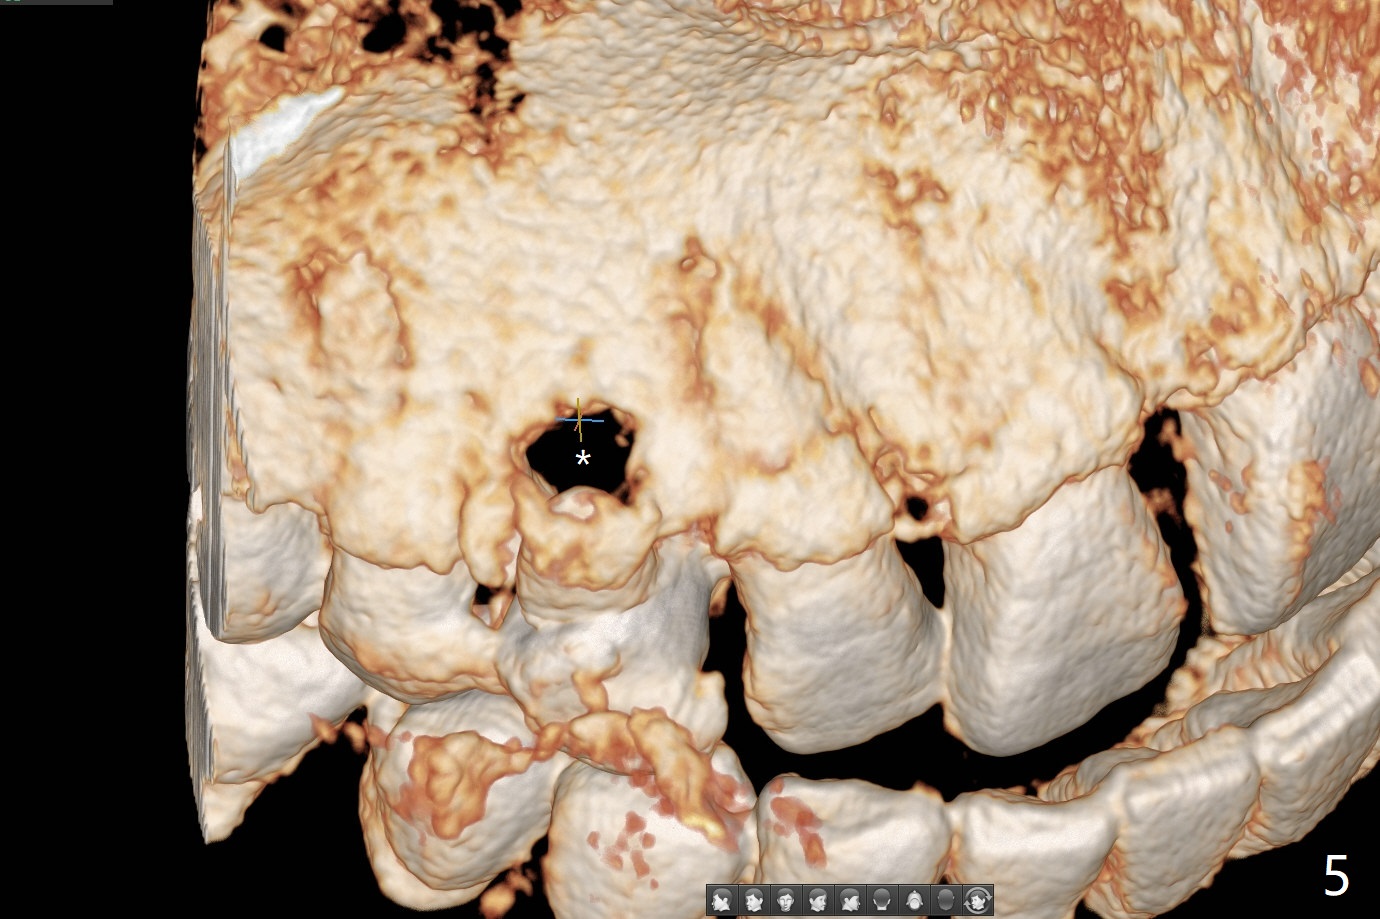

A 52-year-old man requests extraction of the mobile deciduous canine for implant (Fig.1). Use sticky bone (Fig.2 red) to maintain the canine prominence (>). In fact, there is apical perforation of the deciduous canine (Fig.3-5: *). Before bone graft, place a small piece of PRF for repair. The patient refuses to close the diastema between #8 and 9 (Fig.4 ^). Since the cancellous bone is 2.9 mm (Fig.3), it is safe to place a narrow implant (Fig.7). Return to Protect Graft Clindamycin 手术 15 Xin Wei, DDS, PhD, MS 1st edition 04/28/2021, last revision 05/27/2021